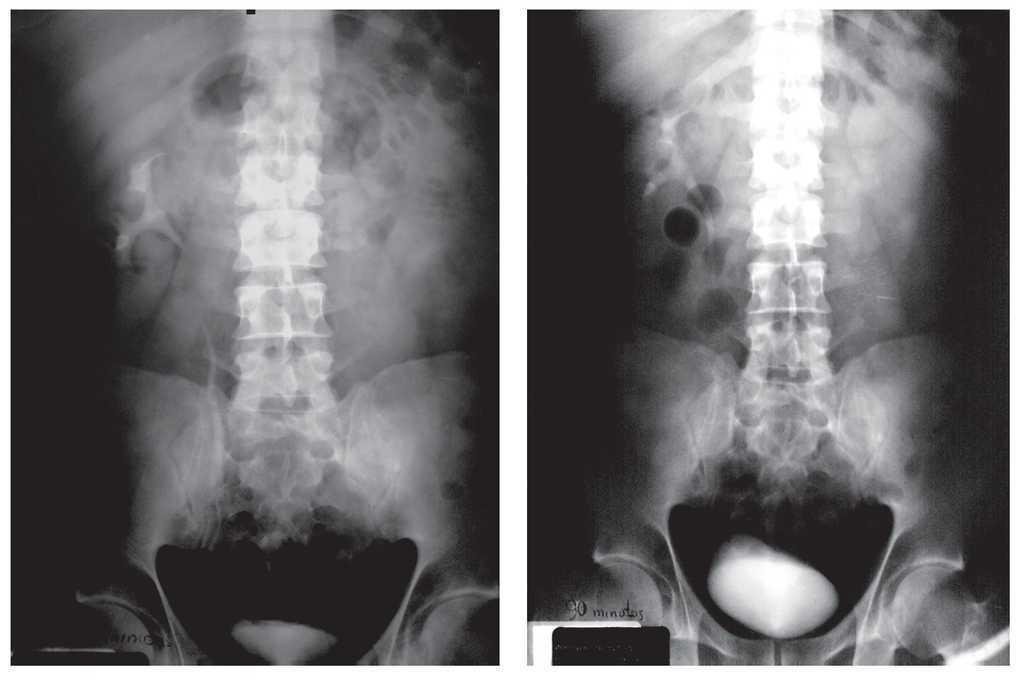

El resultado microscópico señaló: cortes con hematoxilina-eosina en parénquima renal y sistema pielocaliceal proceso inflamatorio crónico granulomatoso caseificante y zonas de esclerosis glomerular y tiroidización de túbulos renales, persistiendo en bordes quirúrgicos (uréter), necrosis caseosa y destrucción del urotelio. Conclusiones: Pielonefritis crónica granulomatosa con proceso fímico, bordes quirúrgicos con proceso inflamatorio crónico granulomatoso (Figura 3). Cultivo de la secreción renal: positivo para Mycobacterium tuberculosis.

Imagen 3. Corte histológico de la pieza quirúrgica, que muestra pielonefritis crónica granulomatosa con proceso fímico.